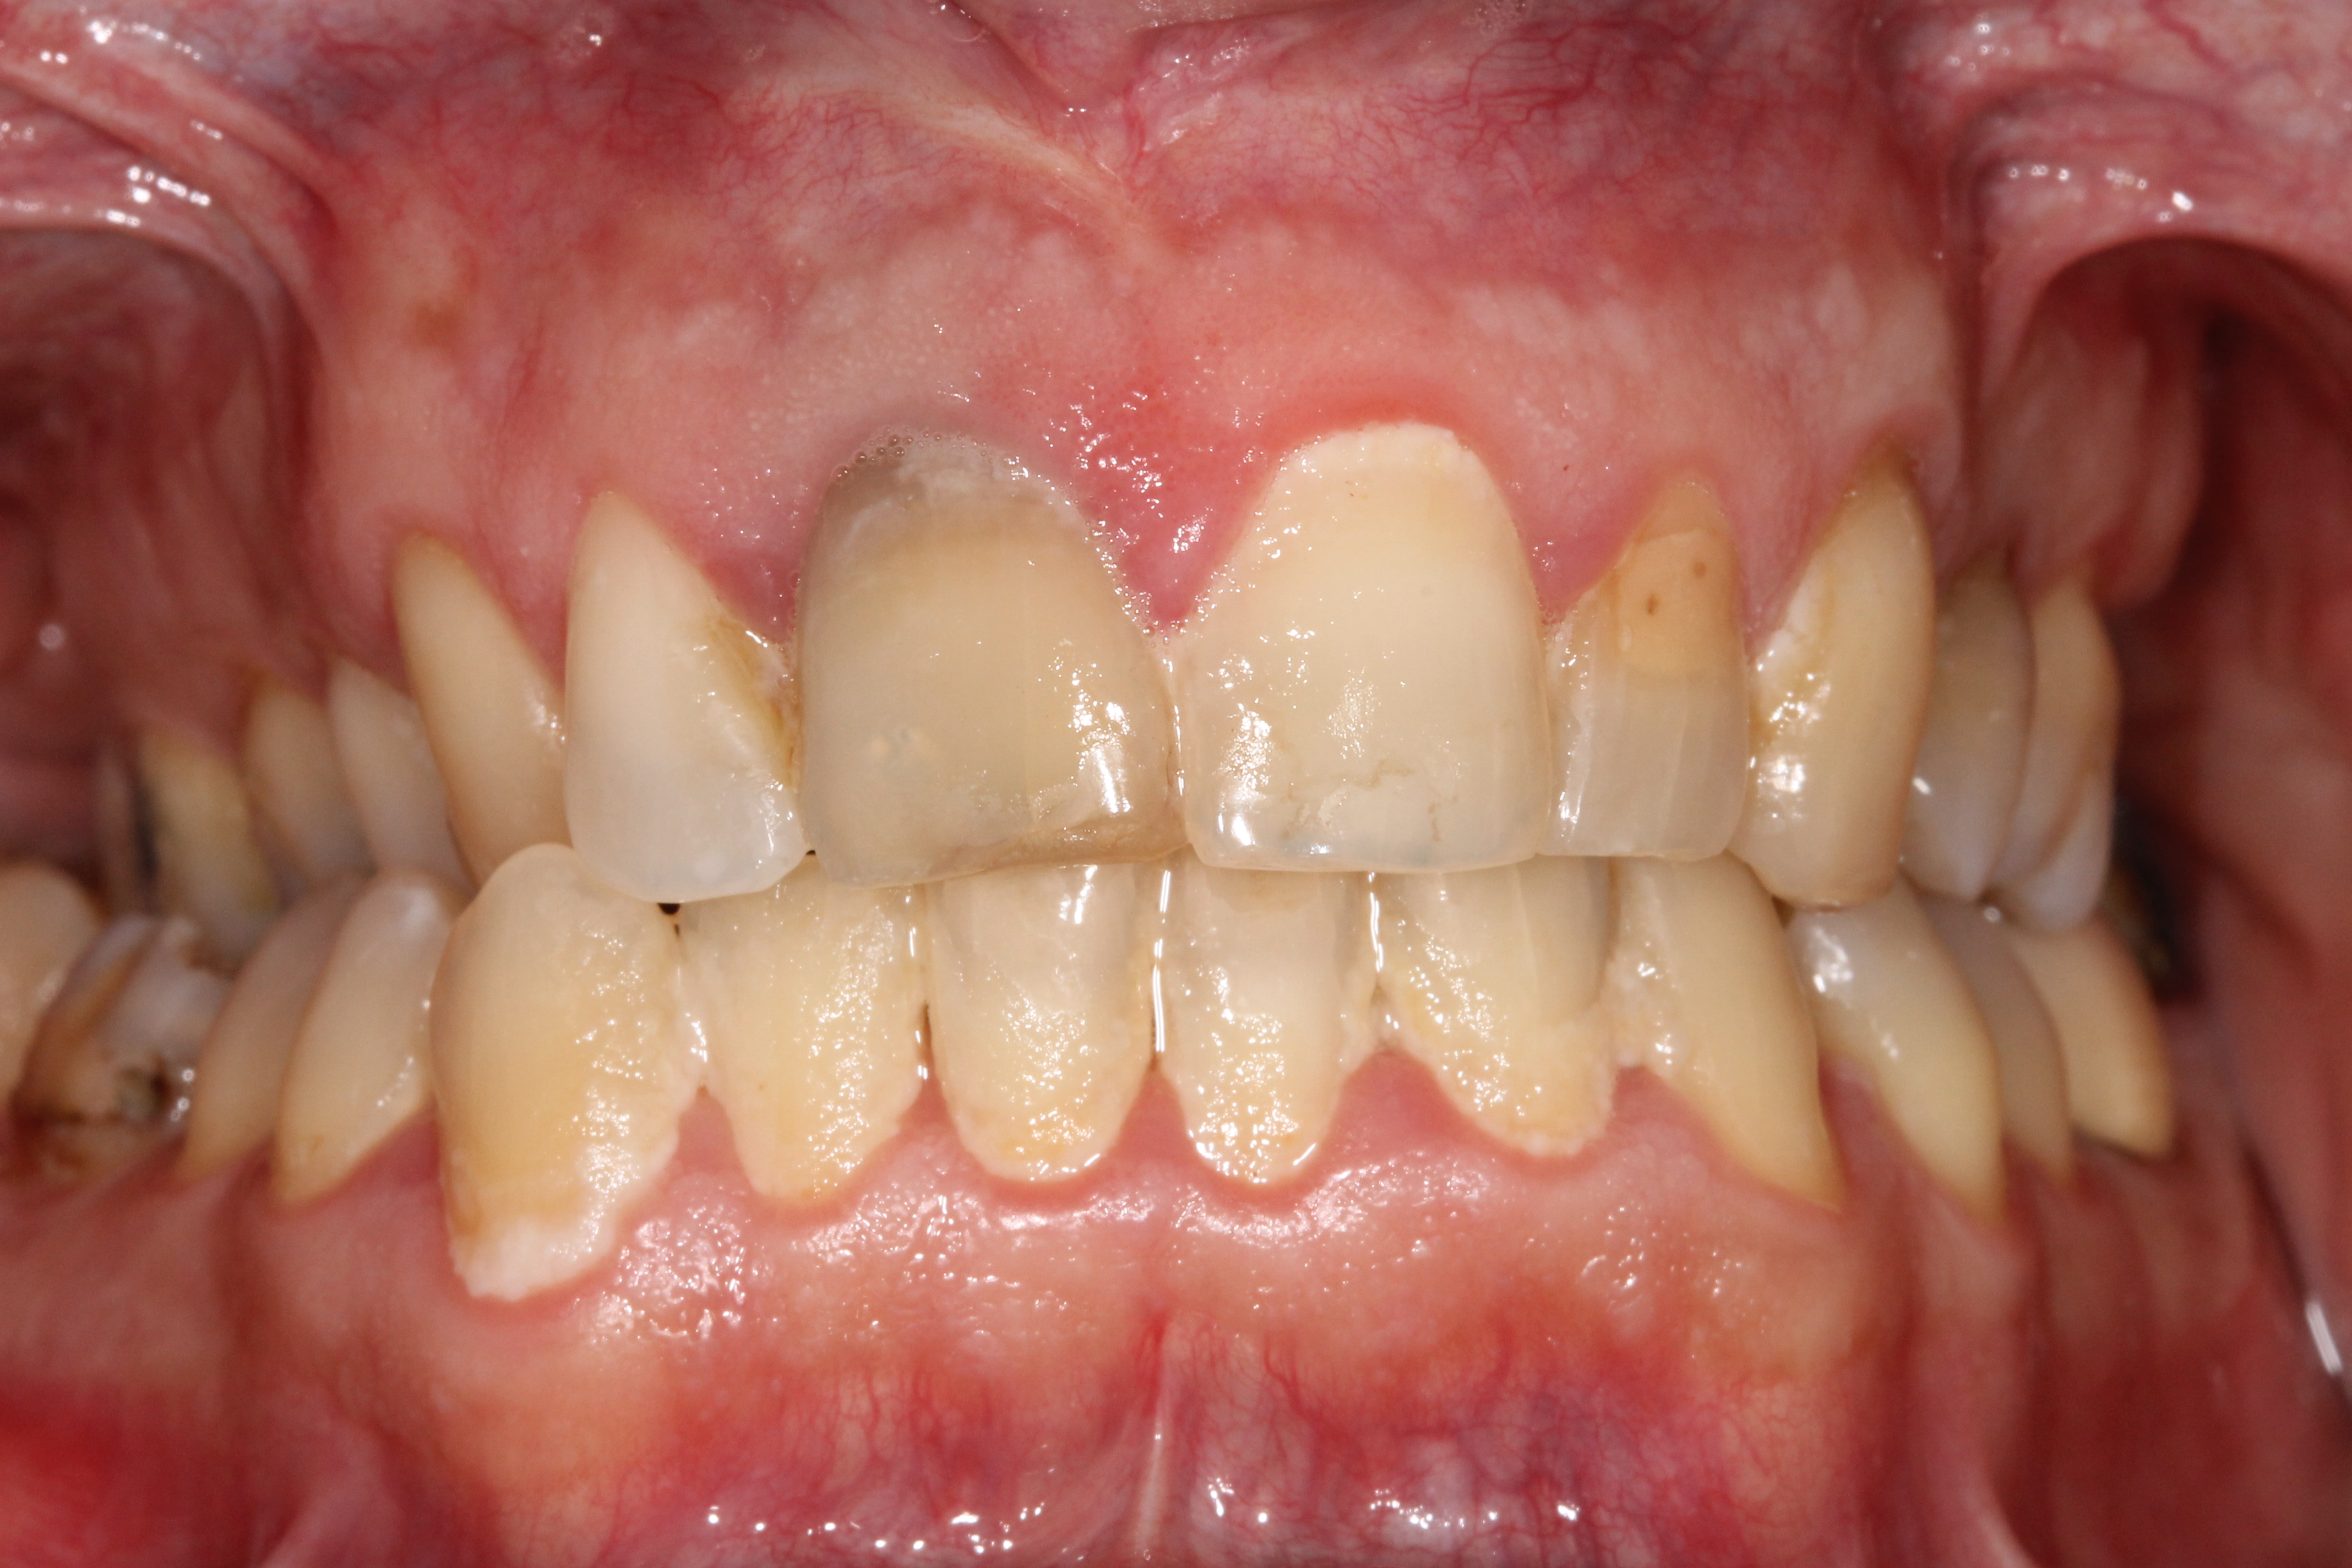

ΕΝΔΕΙΚΤΙΚΑ ΠΕΡΙΣΤΑΤΙΚΑ ΤΗΣ ΝΟΣΟΥ

αρχικό στάδιο

Ουλίτιδα

Η ουλίτιδα είναι η φλεγμονή μόνο των ούλων και αποτελεί την αρχική μορφή της περιοδοντικής νόσου.

Στην ουλίτιδα, μετά τη θεραπεία, οι περιοδοντικοί ιστοί επανέρχονται στην αρχική φυσιολογική τους μορφή (αντιστρεπτή βλάβη). Εάν όμως δεν θεραπευτεί, στις περισσότερες περιπτώσεις η ουλίτιδα, και σε χρόνο που δεν γνωρίζουμε και δεν μπορούμε να προβλέψουμε, εξελίσσεται σε περιοδοντίτιδα.